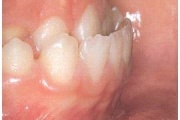

Hambakaaries

Lutipudelikaariese kahjustused

Lutipudelikaaries